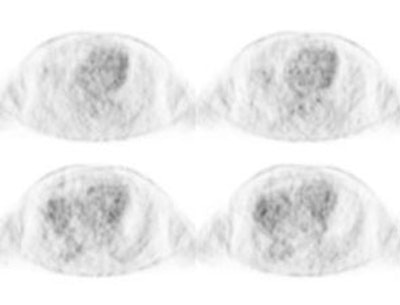

PET: Studies indicate that round atelectasis is not metabolically active on FDG-PET imaging [7].

Round atelectasis on PET FDG imaging: The images below demonstrate the typical CT and FDG PET findings in round atelectasis. On CT, there are thickened lung markings and vessels which swirl into the lesion that abuts an area of pleural thickening. Note the lack of metabolic activity in round atelectasis on PET imaging. |